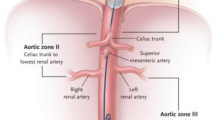

For the use of REBOA, the aorta is divided in three anatomical zones. Occlusion in zone I, from the left subclavian artery (LSA) to the celiac trunk (CT), is used for abdominal hemorrhage control or as pressure support in cardiopulmonary resuscitation for cardiac arrest of various etiology. Zone III, the infrarenal aorta, is targeted in case of pelvic or junctional inguinofemoral (groin) bleeding. Zone II comprises the visceral artery branches and is currently considered a no-go zone that should be actively avoided.

The software program 3Mensio Vascular™ (Pie Medical Imaging BV, Maastricht, The Netherlands) was used to create a 3D-reconstruction of the aorta and iliofemoral trajectories and construct a central luminal line (CLL) within this vasculature (Fig. 1). By measuring along the central axis of the aorto-iliofemoral lumen, zone lengths and intravascular distances from the femoral arterial access points (FAAP) to the zone boundaries could be determined. The right and left CFA at the mid-femoral head level were chosen as the FAAP and starting points for the distance measurements [17,18,19, 23]. The REBOA-zones were defined by the major aortic branches which represent the zone boundaries. Zone III length was the distance between the aortic bifurcation (AB, inferior boundary of zone III) and the distal origin of the lowest main renal artery (RA, superior boundary of zone III). Zone II extended from the lower RA to the CT. Zone I ranged from the proximal origin of the CT (inferior boundary of zone I) to the distal origin of the LSA (superior boundary of zone I). Aortic diameters and the depth of the left CFA, defined as the shortest distance from the skin, were also measured. Two authors (JvdV and BV) performed the measurements.

Representative images of the intravascular distances measurement method with a 3D-reconstruction of the aorta and iliofemoral trajectory (a), construction of a central luminal line (b & c) and the stretched vessel configuration in coronal (d) and sagittal (e) anatomical plane with zone III (blue shaded region) and II (orange shaded region). The dotted lines represent the mid-femoral head (red), aortic bifurcation (green), distal origin of lowest renal artery (blue) and proximal origin of celiac trunk (orange) levels